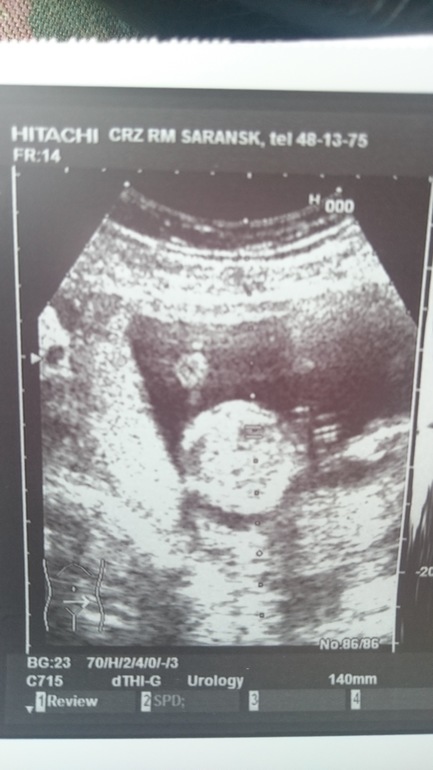

УЗИ, КТГ, доплерСходила на УЗИ. С малышом все хорошо! 17 неделек. Сидим пока на попе и ножками пипку прикрываем)) Но узист почти уверено сказал, что это девочка) И толи в подтверждение своих слов, толи от жажды к фотографированию, сделал снимок крохи) Теперь ВНИМАНИЕ вопрос: где какие части тела на фото?))) под кат.

Это голова по центру круглая? А тело где? Учитывая продольное тазовое предлежание.. В общем, ваши версии, девочки!

Снизу плацента, а кружок-может и животик) голова другую структуру имеет. Узисту за фото 2 балла!)))

Ну, если включить мышление и фантазию, то да, круглое - голова, подбородком получается себе на грудь упирается, и ото внизу тело, а то что справа, то наверно ноги, может махал малыш ими и получилось так размыто. Нам когда в 14 недель второе фото делали, узис стразу сказал, вы думаете так легко кадр поймать, он же там не лежит и не позирует))) Так что не знаю точно про девочку, но непоседа точно, судя по фото))))))))))))))))

Под кругляшком-головой там ручка 😊 локоток ведь видно даже. Пальчик большой видно 😊 как-будто 👍 показывает так 👍 но скорее всего просто пальчики растопырил малышастик. Ну,а остальное непонятно... Может пуповина там,где про ноги думают все..

..а..нет.. Я пригляделась. Там ножки на самом верху. Посмотрите. Получается вид как будто когда о стенку ноги обопрешь и лежишь 😊 и кулачки там

Леночка , я в таких снимках не ахти) но вижу картинку как будто голова круглая , где ты и имеешь ввиду , все остальное идёт справа, как будто лежит на животике а ручки под головой, а в конце одна ножка приподнята) балерина вобщем))счастья вам и здоровья крепкого)))